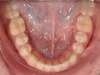

Absence congénitale des incisives latérales supérieures. Appareils fixes pour créer l’espace nécessaire à la mise en place de facettes en remplacement des latérales.

Après